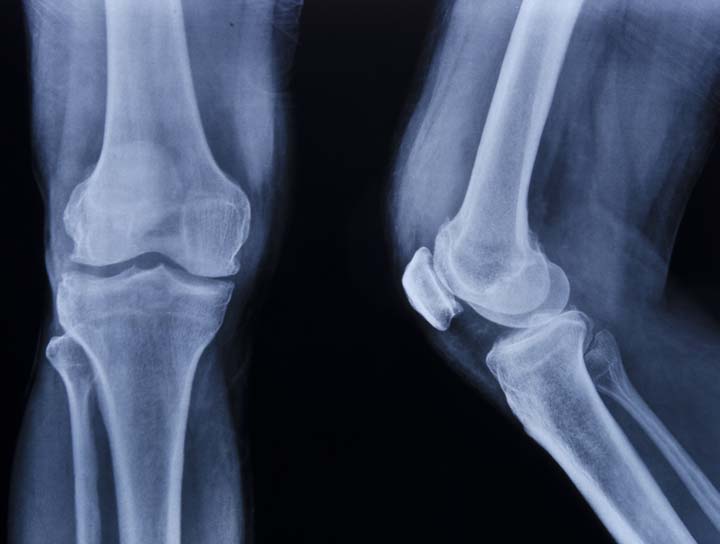

Osteoarthritis is due to Wear and Tear of the cartilage.

With age our cartilage loses the resilience and undergoes degeneration.

Fractures or ligament injuries through the joint where the cartilage is also injured.